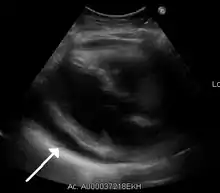

| A 2D echo transthoracic echocardiogram of pericardial effusion. The "swinging" heart. | |

ECG: may present with sinus tachycardia, low voltage QRS as well as electrical alternans.[2] Due to the fluid accumulation around the heart, the heart is further away from the chest leads, which leads to the low voltage QRS. Electrical alternans signifies the up-and-down change of the QRS amplitude with every beat due to the heart swinging in the fluid (as displayed in the ultrasound image in the introduction) .[1] These three findings together should raise suspicion for impending hemodynamic instability associated with cardiac tamponade.

Echocardiogram (ultrasound): when pericardial effusion is suspected, echocardiography usually confirms the diagnosis and allows assessment of the size, location and signs of hemodynamic instability.[6] A transthoracic echocardiogram (TTE) is usually sufficient to evaluate pericardial effusion and it may also help distinguish pericardial effusion from pleural effusion and MI. Most pericardial effusions appear as an anechoic area (black or without an echo) between the visceral and the parietal membrane.[1] Complex or malignant effusions are more heterogeneous in appearance, meaning they may have variations in echo on ultrasound.[4] TTE can also differentiate pericardial effusion based on the size. Although it's difficult to define size classifications because they vary with institutions, most commonly they are as follows: small <10, moderate 10–20, large >20.[4] An echocardiogram is urgently needed for evaluation when there is concern for hemodynamic compromise, a rapidly developing effusion or history of recent cardiac surgery/procedures.[1]

A large anechoic (black) pericardial effusion as seen on ultrasound. Closed arrow: the heart, open arrow: the effusion